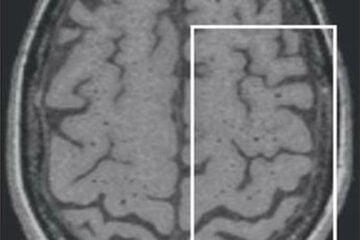

Cerveau : les différences gauche-droite cartographiées

Article dans “Cerveau et Psycho” par Emmanuel Mellet et Michel Thiebaut de Schotten

Sciences participatives : analyser des images IRM pour faire avancer la science

Published on 12 May 2021

Vincent Planche et al., in Alzheimer’s & Dementia

Clinical relevance of brain atrophy subtypes categorization in memory clinics